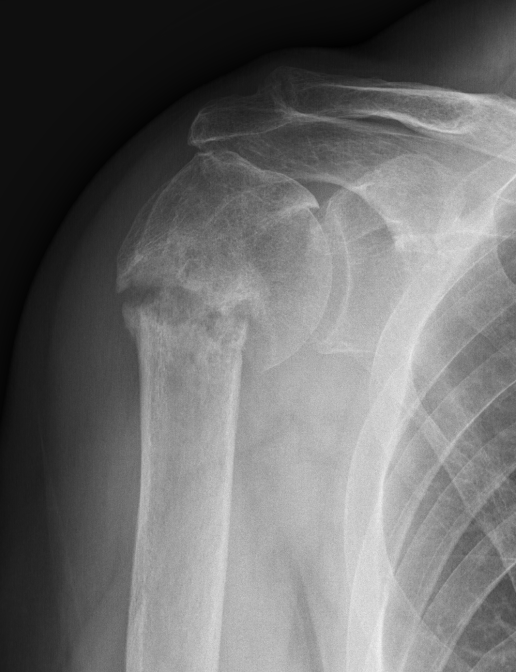

Two part

Displaced greater tuberosity fracture

Displaced lesser tuberosity fracture

Two part proximal humerus fracture

Two part proximal humerus fracture dislocation posterior